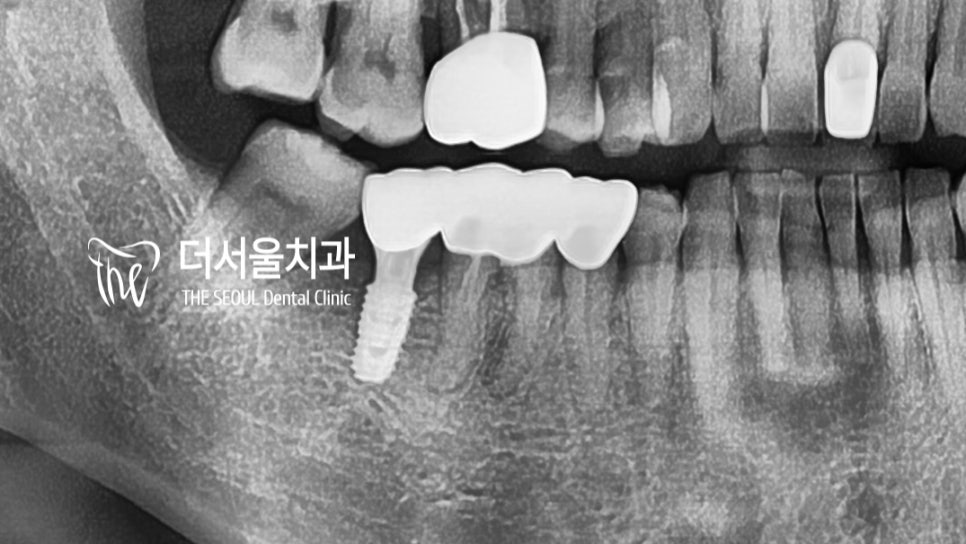

한눈에봐도 깔끔한 지르코니아 크라운으로

바껴 있는 것을 확인할 수 있네요.

이전에 비해 훨씬 심미적으로 뛰어난

구강 내를 볼 수 있습니다.

『어? 반대쪽도 교체를..?』

과정을 마무리하려던 찰나,

“저 반대쪽도 불편한데,

이곳도 바꾸고 싶어요!!”

라는 말씀을 남겨주셨던 환자 분ㅎㅎ

바뀐 보철이 편안하셨는지

반대쪽도 교체를 원하셨는데요.

사실 예전에 진료를 받았을 때에는

이곳은 식립이 어렵다며 켄틸레버 브릿지를

하게 되었다던 환자 분,

어려운게 어디있습니까!

더서울에서는 그런건 없습니다.

할 수 있을 때까지 해봐야죠!!

임플란트 잘하는치과 로 찾아와주셨으니

이곳도 교체를 해보기로 했습니다!!

이곳도 컴퓨터 분석을 통해 정밀 계획을 세운 뒤!

정해진 위치에 깔끔하게 심어드렸습니다^^